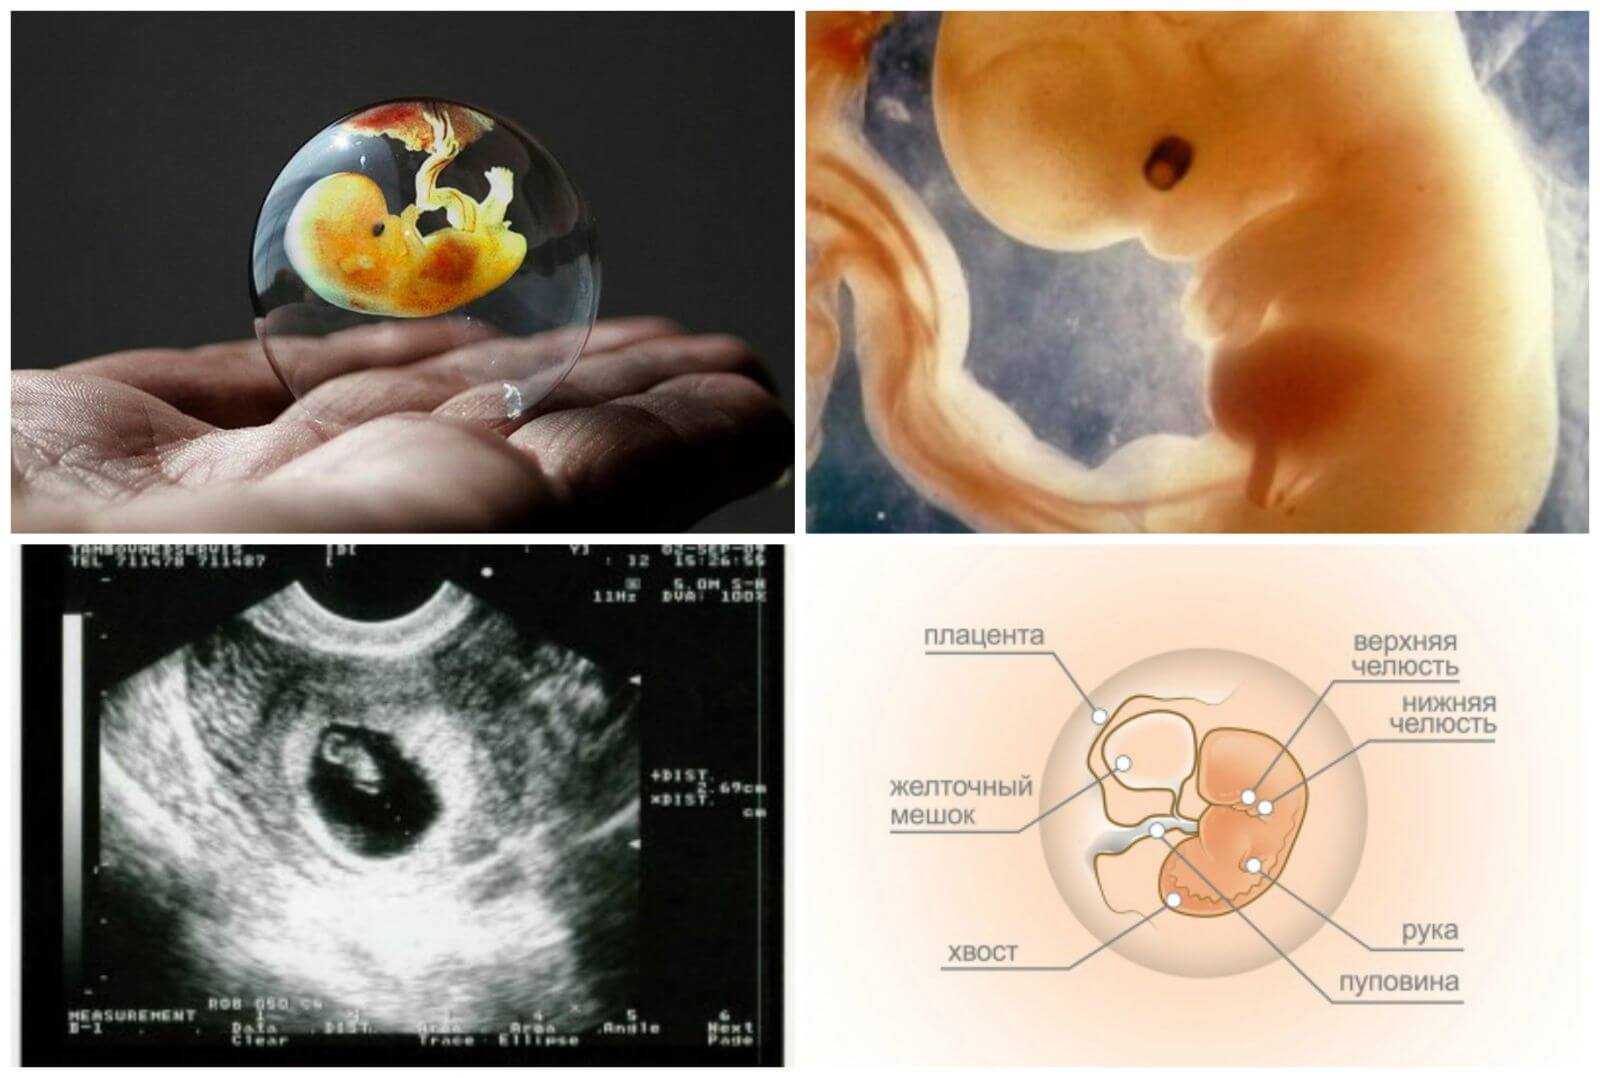

Развитие эмбриона на 8 неделе беременности

Раздел: Картинки на заметку